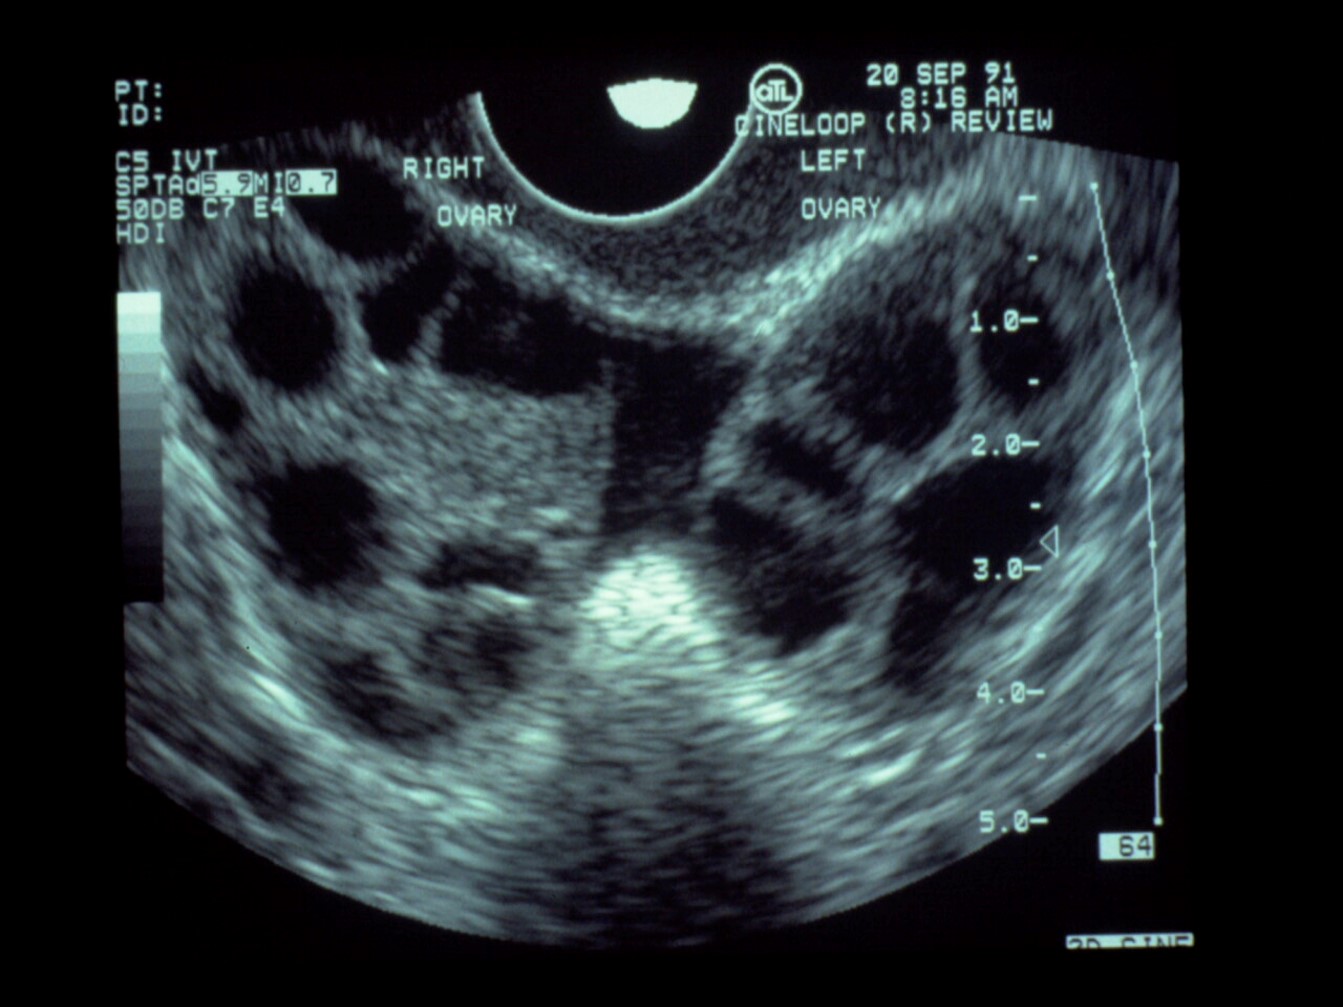

Infertility Treatment: Ovulation Induction and Insemination

- PCOS Letrozole is considered as the first-line treatment for ovulation induction for patients with PCOS.

- Luteal support: Luteal progesterone support is beneficial to patients undergoing gonadotropin stimulation and intrauterine insemination

- Unexplained Infertility: Gonadotropin treatment is associated with a significantly elevated risk of multiple gestations gestations